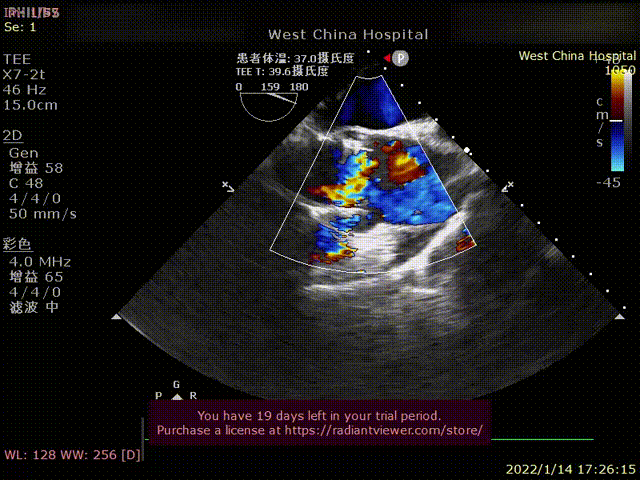

患者为70岁女性,因“心悸、胸闷16余年,反复1年,加重1天 “主诉入院。术前超声提示左心增大,左室为著,LVDD 71mm,LVEF 41%,主动脉瓣中重度反流。术后即刻主动脉瓣大量反流消失,LVDD 62mm,左心较术前明显缩小。

术后超声1

术后超声2